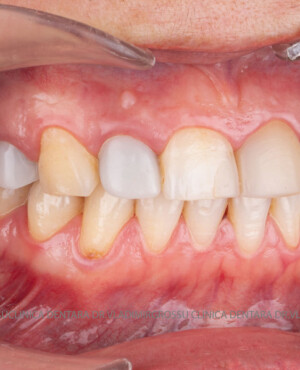

Restaurări cu coroane din zirconiu vs fațete ceramice

Atât fațetele ceramice (Emax sau 360) cât și coroanele din zirconiu sunt soluții estetice eficiente. Fațetele sunt indicate pacienților cu o poziție dentară relativ uniformă și dinți vitali, deoarece implică șlefuirea minimală a smalțului (0,4–0,7 mm) și fixarea adezivă sub coferdam. În cazurile cu dinți tratați endodontic, coroane pigmentate, proteze pe implanturi sau când este necesară o creștere semnificativă a ocluziei, se preferă coroanele din zirconiu.